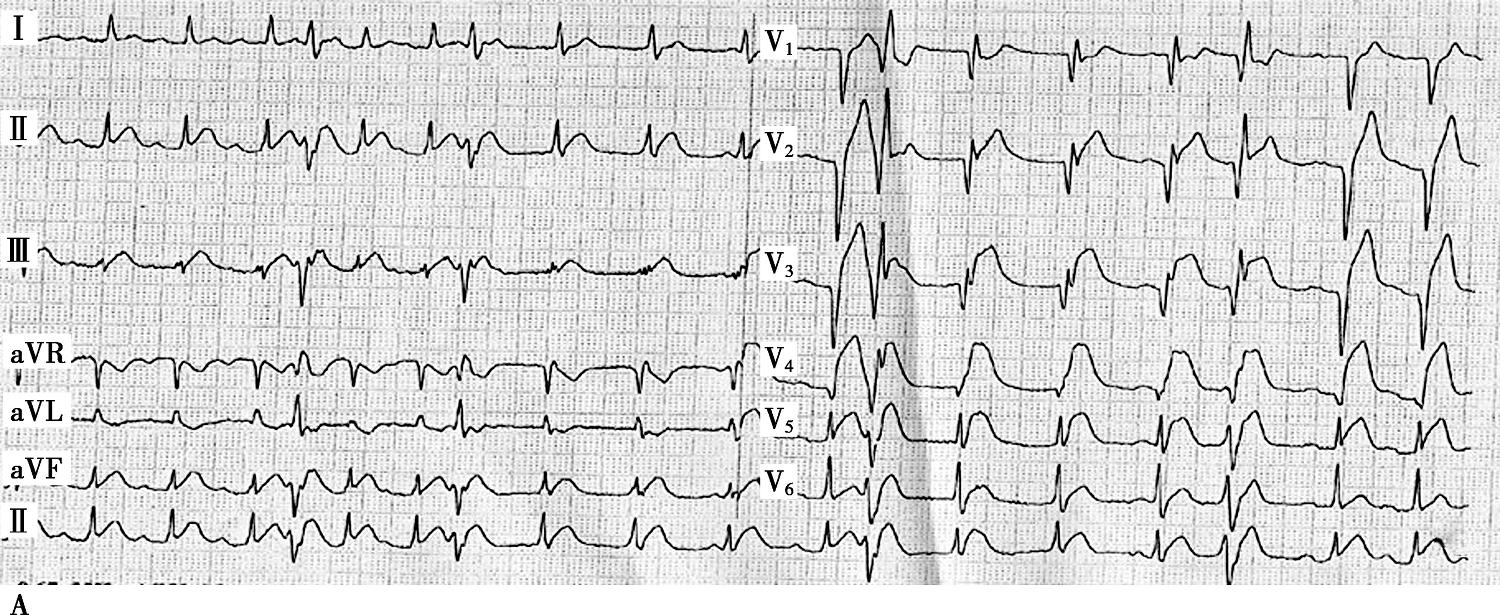

图1当地心电图及急诊PCI结果

A.当地市医院急诊心电图提示:Ⅱ、Ⅲ、aVF、V2~V5导联ST段弓背向上抬高;B.急诊造影提示:LAD开口闭塞,回旋支远段栓塞;C.PCI术后,LAD TIMI 2级,LCX远段血流未恢复